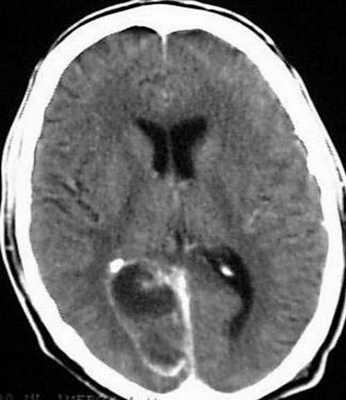

Точность диагностирования с помощью КТ головного мозга зависит от стадии формирования абсцесса. На ранних стадиях заболевания диагностика затруднена. На этапе раннего энцефалита (1-3 сутки) КТ определяет зону сниженной плотности неправильной формы. Введенное контрастное вещество накапливается неравномерно, преимущественно периферических отделах очага, реже в центре.

На более поздних этапах энцефалита контуры очага приобретают ровные округлые очертания. Контрастное вещество распределяется равномерно, по всей периферии очага; плотность центральной зоны очага при этом не меняется. Однако на повторной КТ (через 30-40 минут) определяется диффузия контраста в центр капсулы, а также наличие его и в периферической зоне, что не характерно для злокачественных новообразований.

Инкапсулированный абсцесс мозга на КТ имеет вид округлого объемного образования с четкими ровными контурами повышенной плотности (фиброзная капсула). В центре капсулы зона пониженной плотности (гной), по периферии видна зона отека. Введенное контрастное вещество накапливается в виде кольца (по контуру фиброзной капсулы) с небольшой прилежащей зоной глиоза.

На повторной КТ (через 30-40 минут) контрастное вещество не определяется. При исследовании результатов компьютерной томографии следует учесть, что противовоспалительные препараты (глюкокортикостероиды, салицилаты) в значительной степени влияют на скопление контраста в энцефалитическом очаге.

Для того чтобы провести точную диагностику места расположения абсцесса мозга и мозжечка, проводят компьютерную и магнитно-резонансную томографию головного мозга. При проведении компьютерной томографии выявляется тонкая, гладкая стенка абсцесса, которая имеет правильные контуры. Магнитно-резонансная томография позволяет также определить капсулу абсцесса. Если нет возможности провести вышеперечисленные виды исследования, можно провести пневмоэнцефалографию или радиоизотопную сцинтиграфию головного мозга.

Диагностика • Как и при подозрении на любое объёмное образование головного мозга, в первую очередь следует сделать КТ. Чувствительность метода приближается к 100%, специфичность значительно ниже, во многом зависит от стадии формирования абсцесса •• 1 стадия — ранний церебрит: 1-3 день, начало развития инфекционно-воспалительного процесса, отсутствие демаркации от окружающего здорового мозга, токсические изменения в нейронах, периваскулярные инфильтраты. Сопротивление при пункции умеренное •• 2 стадия — поздний церебрит: 4-9 день, выпадение в очаге ретикулярного матрикса, появление центрального некроза. Сопротивление при пункции отсутствует •• 3 стадия — ранняя инкапсуляция: 10-13 день, появление неоваскуляризации, выраженного некротического центра, по периферии формируется соединительнотканная капсула (она обычно тоньше со стороны желудочка). Сопротивление при пункции отсутствует •• 4 стадия — поздняя инкапсуляция: после 14 дней, чёткая коллагеновая капсула, некротический центр, зона глиоза вокруг капсулы. Сопротивление при пункции сильное, в момент прокола капсулы ощущение «провала» • Дифференциальную диагностику проводят между глиобластомой и метастазом.

абсцесс мозга на снимке

КТ головного мозга — доступный и высокочувствительный метод. Без контрастирования он определяет лишь зону пониженной плотности. Структура патологического очага становится четкой только под воздействием рентгеноконтрастного вещества.